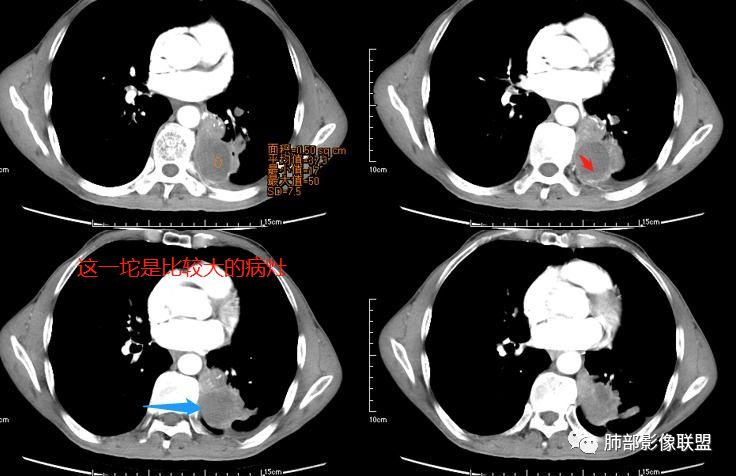

这个病灶如何分析?

张小兵:与血管关系密切

三个石头:都有血管从凹陷处进入

张玉:收缩,牵拉,血管增粗,与血管相连

南边:我们再看看左下叶背段的病灶

南边:

液化,而不像坏死,是有强化的;这个里面似有液平。说明里面有分泌粘液?

主要考虑在GPA和粘液性癌里面

无发热,其他慢性细菌先不考虑,有的低毒的,但是结节形态还是比较不规则的,分布也是比较随机,更像原发病灶。真菌方面,结节没有融合,坏死也是液化坏死,不符合隐球菌,曲霉不符合IPA,慢性吸入的也少见。结核没有树丫,不考虑。鉴别主要是GPA,和肺癌。GPA不支持点是皮肤,肾脏没有累及,ANCA不支持。。。肺癌主要是腺癌和鳞癌转移。比较支持的是淋巴结肿大,和左下肺的主病灶,支气管堵塞和异常强化。还有分叶,局部膨隆。可以建议支气管镜检测。

大家按我提的单个病灶分析,很多提出来都是典型的腺癌

脐凹征、粗短毛刺、深分叶、中央结构杂乱

本病例左肺下叶肿块,有深分叶、毛刺、胸膜牵拉凹陷、支气管截断及纵隔内淋巴结肿大等征象,都均支持病灶为恶性,如腺癌,而且叶间裂的多发结节也提示是腺癌来源可能大;双肺多发结节、肿块,大部分病灶有分叶、毛刺及胸膜凹陷的恶性征象,与原发肿瘤本身的性质有关,所以应该与左肺下叶肿块同源,而且双肺多发病灶内空洞也具有多样性;